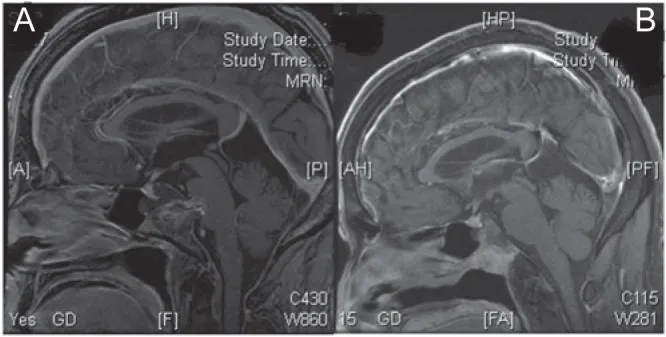

A. 术前矢状位钆增强磁共振成像显示斜坡脊索瘤伴小型硬膜下肿块侵犯脑桥。

B. 通过经口-经腭入路成功切除硬膜下肿瘤。术中对直径7毫米的硬膜缺损进行处理,在保留蛛网膜层前提下未发生脑脊液漏。硬膜缺损采用涂抹纤维蛋白胶的腹部脂肪进行封闭,患者术后未出现脑脊液漏。